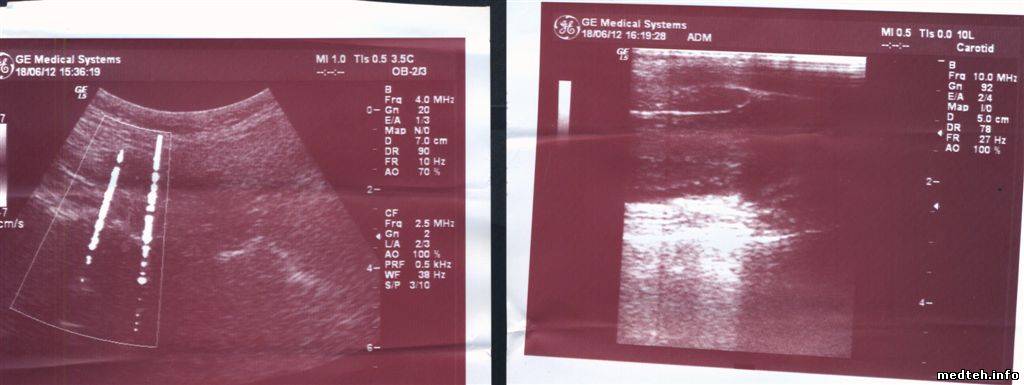

Здраствуйте!Я доктор,работаю на аппарате Logiq 500pro 2006 года выпуска.За время работы на аппарате отмечаются значительные помехи,которые периодически сами пропадают.Работаю в кабинете возле которого есть лифт,хирургическая операционная и еще один узи кабинет.Для устранения этих помех был установленный ИБП Power walker VI 2200,установили сетевой фильтр,заземление от розетки.Но ничего не помагает.Пробывали перетаскивать на другую сторону помещения,но без эффекта. Вот вылаживаю фото:

Подскажите ,пожалуйста,в чем причина этих помех?

4219416.jpg (151.7 Kb) · 2585506.jpg (160.1 Kb) · 7010616.jpg (166.3 Kb) · 0486875.jpg (125.6 Kb)

А у вас помехи только на конвексе или и на других датчиках такое присутствует?

на всех датчиках присутствует